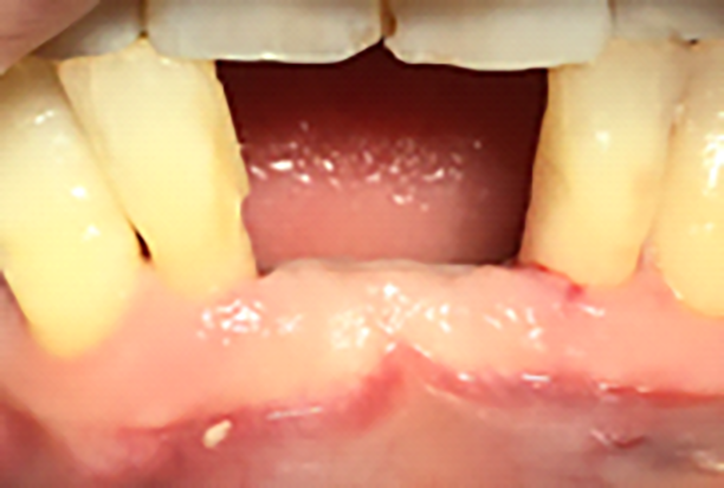

Si presenta alla nostra attenzione una paziente di 40 anni lamentando sensibilità, dolore alla masticazione e mobilità a carico degli incisivi centrali dell’arcata inferiore. Previa anamnesi medica e odontoiatrica si procede con l’esame obiettivo e con gli esami radiografici. Dall’esame obiettivo si osserva come gli elementi 3.1 e 4.1 risultino mobili, dalla radiografia si evidenzia un notevole riassorbimento osseo attorno agli elementi dentari in questione.

Previa anestesia locale si esegue lo scollamento di un lembo a spessore totale per consentire l’avulsione atraumatica degli elementi 3.1 e 4.1 (figure 1a-1b). Si revisionano le cavità alveolari e si posizionano osso bovino deproteinizzato e una membrana di collagene riassorbibile. Si sutura con filo 5/0, si posiziona un maryland bridge per garantire l’estetica in attesa dell’inserimento implantare e si esegue una radiografia di controllo (figure 2-4).